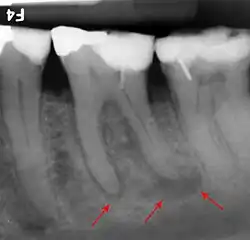

Apical periodontitis is acute or chronic inflammation around the apex of a tooth caused by an immune response to bacteria within an infected pulp.[23] It does not occur because of pulp necrosis, meaning that a tooth that tests as if it's alive (vital) may cause apical periodontitis, and a pulp which has become non-vital due to a sterile, non-infectious processes (such as trauma) may not cause any apical periodontitis.[12]: 225 Bacterial cytotoxins reach the region around the roots of the tooth via the apical foramina and lateral canals, causing vasodilation, sensitization of nerves, osteolysis (bone resorption) and potentially abscess or cyst formation.[12]: 228

The periodontal ligament becomes inflamed and there may be pain when biting or tapping on the tooth. On an X-ray, bone resorption appears as a radiolucent area around the end of the root, although this does not manifest immediately.[12]: 228 Acute apical periodontitis is characterized by well-localized, spontaneous, persistent, moderate to severe pain.[15]: 125–135 The alveolar process may be tender to palpation over the roots. The tooth may be raised in the socket and feel more prominent than the adjacent teeth.[15]: 125–135

- Radiographs utilized to find dental caries and bone loss laterally or at the apex.